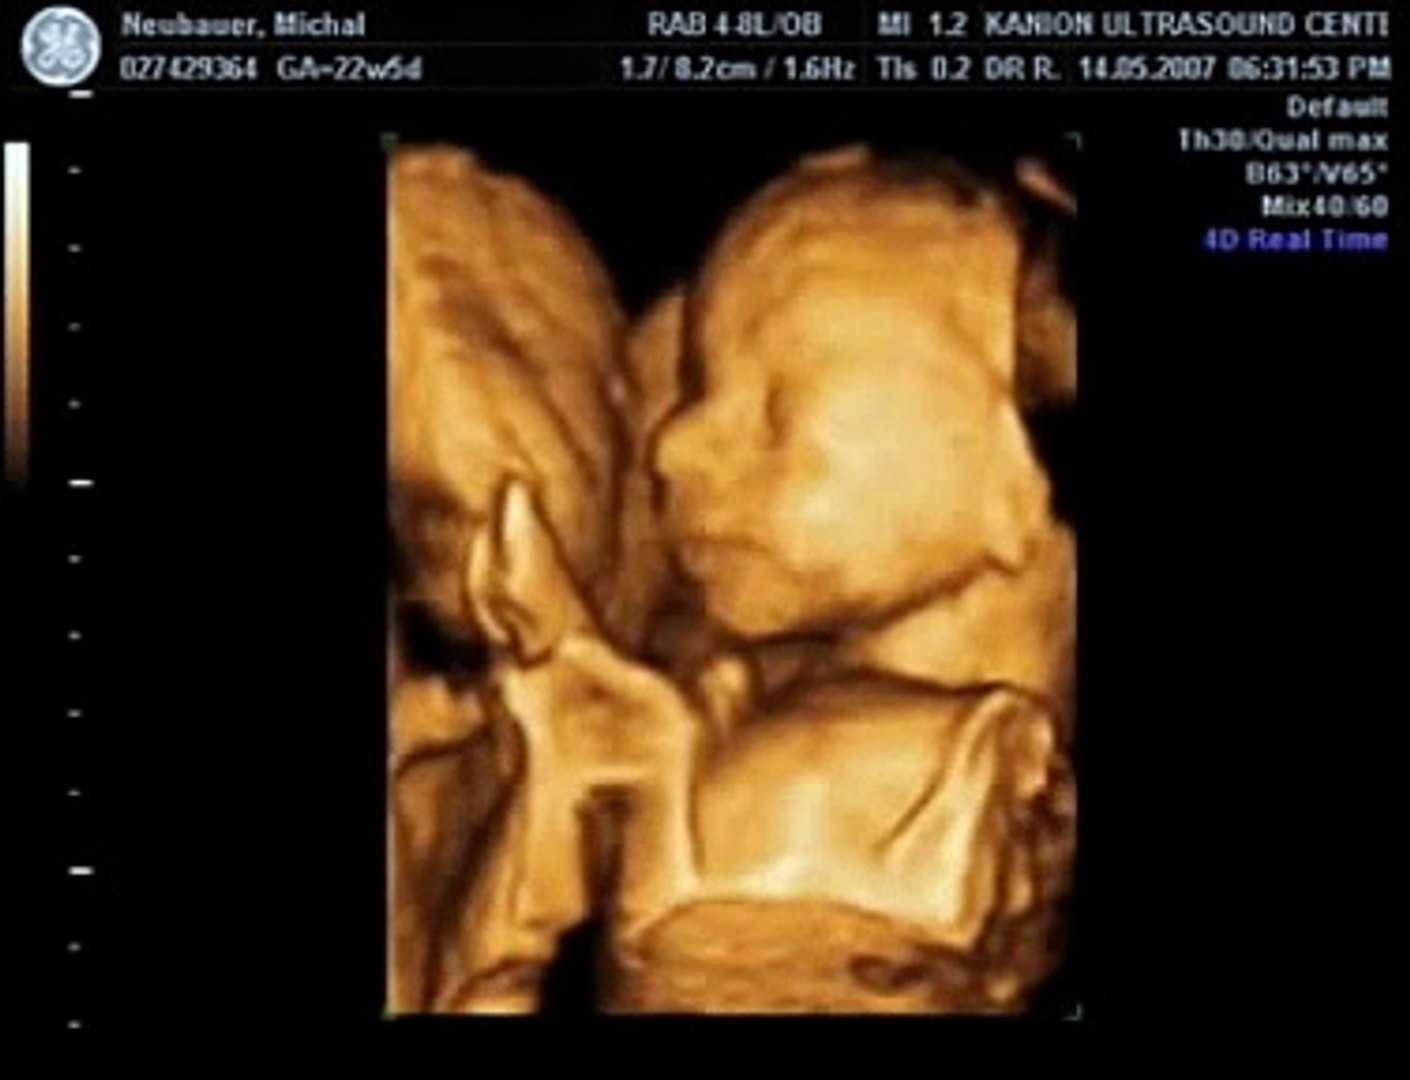

23 Week 3d Ultrasound

3d 5d ultrasound images and 4d ultrasound video can be obtained at any stage. Here is a clip of a tiny yet mighty baby at just 23 weeks. You can find more details about your baby if you opt for a 3d or 4d ultrasound they may be expensive and give better results only if your baby is in a favorable position at the time of scan. Week 23 ultrasound with the baby to be crouched and her legs pulled in toward her chest you can almost see her complete profile.

In 23 weeks pregnant ultrasound you will see your baby sucking on his thumb and moving arms and legs slowly. Baby development at 23 weeks. We use the technology of 3d 4d ultrasounds to capture these beautiful moments of babies before call. However we do recommend a gestational age of 26 34 weeks for the best facial detail.

At first your babys ears can hear only low pitched sounds meaning she can hear male voices more clearly than female voices. At this stage the baby has put on some weight and filled out to make features more visible yet still enough fluid in front of babys face to obtain great images.